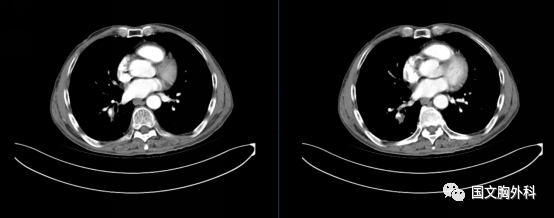

入院時胸部CT,提示:胸部CT平掃+增強:右肺下葉占位,符合肺癌表現(xiàn),伴周圍阻塞性肺炎??v隔、右肺門稍大淋巴結(jié),轉(zhuǎn)移不除外。

治療前 ↓